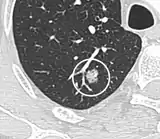

- Margin morphology: a spiculated margin is a risk factor for cancer.[8] Benign causes tend to have a well defined border, whereas lobulated lesions or those with an irregular margin extending into the neighbouring tissue tend to be malignant.[10] In particular, spiculations are highly predictive of malignancy with a positive predictive value up to 90%.[9] Also, a "notch sign", which is an abrupt indentation of the nodule, increases the risk of cancer, but may also be found in granulomatous diseases.[9]

subpleural nodule.[9]

Round well-delineated solid lung nodule with smooth border.[9]

Lobulated nodule.[9]